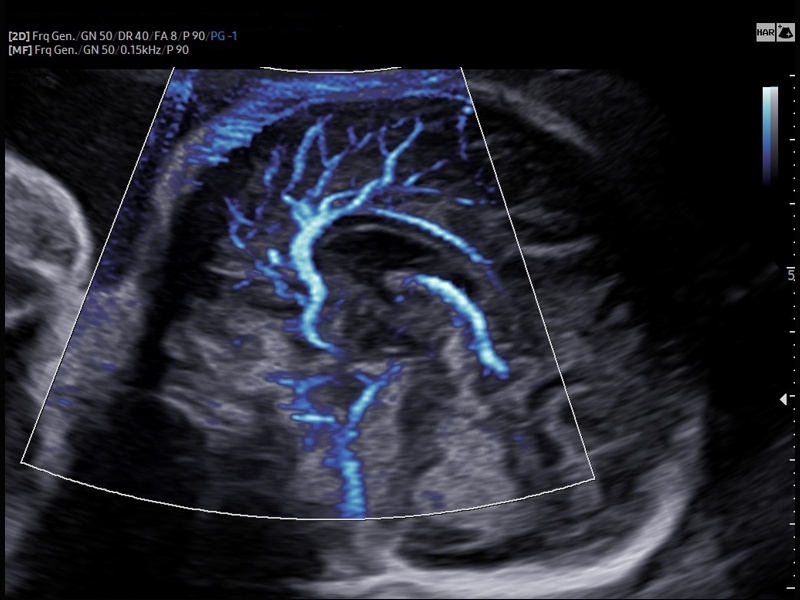

• Модуль MV-Flow – программа (режим), позволяющая визуализировать кровоток в микроциркуляторном русле с высоким разрешением без использования контраста.

• Модуль LumiFlow – программа отображения кровотока с объемной графикой для лучшего понимания архитектоники сосудистого русла.

• Модуль MV-Flow - программа (режим), позволяющая визуализировать кровоток в микроциркуляторном русле с высоким разрешением без использования контраста.

• Акушерство и гинекология

• Модуль Crystal Vue Flow- программа реконструкции прозрачного 3D УЗИ, которое получается при одновременном усилении внутренних и наружных структур. Применяется для визуальной оценки состояния плода и матки, помогает лучше идентифицировать мягкие ткани и кости. Так же визуализирует объемный кровоток.